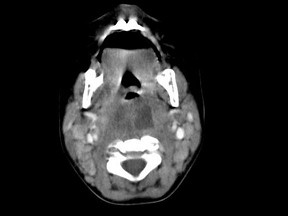

[多选题] 10个月大的婴儿,发热,曾患中耳炎,CT扫描如图所示,正确的描述或诊断是()A .咽后壁软组织肿胀B .其内密度不均C .颈椎骨质未见明显异常D .咽后壁脓肿E .咽后壁寒性脓肿

[多选题] 10个月大的婴儿,发热,曾患中耳炎,CT扫描如图所示,正确的描述或诊断是()A . 咽后壁软组织肿胀B . 其内密度不均C . 颈椎骨质未见明显异常D . 咽后壁脓肿E . 咽后壁寒性脓肿